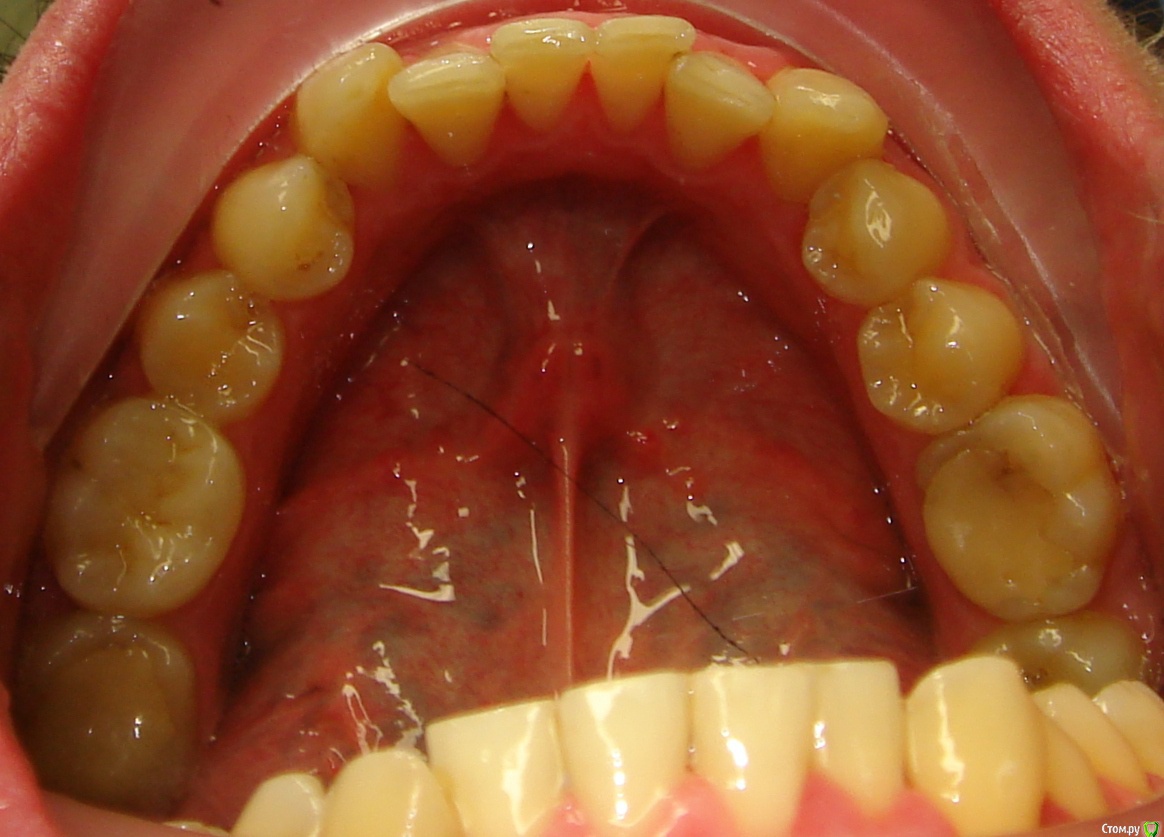

Здравствуйте, Коллеги. Вот такой вот случай, пациент 32 года. Изначально, хотел дистализировать в первом сегменте с целью апрайтинга 13 - 16, провести апрайтинг боковых зубов н/ч, затем САРПЕ и MEAW, понятно, что восьмерки долой еще до лечения. Но потом увидел форму корней 37, 47 (это не искажение, по КТ они и правда такие) и кисты прорезывания за ними. В связи с этим мне кажется, что апрайтинг снизу невозможен, так как эти верхушки никуда меня не пустят, разве что ввиду проблем с пародонтом семерки тоже уйдут. Вопрос: что делать??? Даже если отбросить мультилуп и готовить его на ортогнатию, то апрайт все-равно нужен, как поступить? Заранее спасибо!

P.S.: Забыл... сверху семерки такие же.